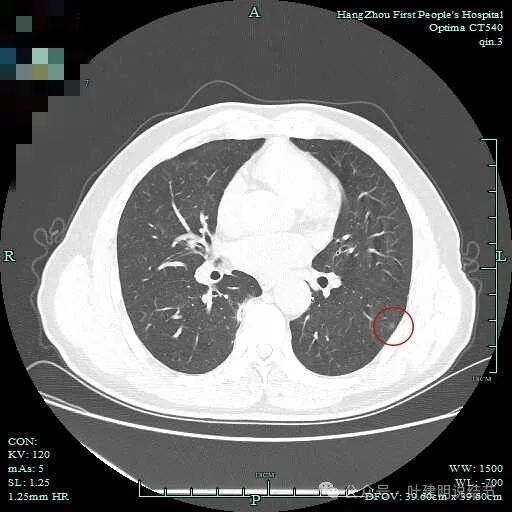

其他病灶情况:

右下脊柱旁怎么也像有磨玻璃结节?但此处正常CT也是略显有慢性炎似的征象的,可这个病人明显结节状,还表面有细毛刺似的。

左下微小磨玻璃结节,胸膜下,轮廓与界限较清,像肺泡上皮增生。

左上胸膜下实性微小结节,缺乏膨胀性,考虑良性;右上叶微小淡磨玻璃结节似的,但太小,不确切。